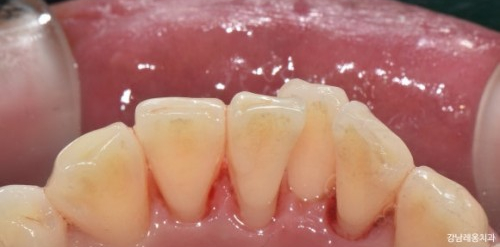

Q. 스케일링 하고 나면 출혈, 이시림

잇몸이 내려가 보이는 등

오히려 안 좋은 것 같아요.

❗

이는 스케일링에 대한 대표적인 오해입니다.

스케일링 중 출혈은 치석이 오래 쌓이면서

잇몸이 약해지고 작은 자극에도

쉽게 피가 나는 상태이기 때문입니다.

또한 이시림은 치아 표면에 붙어 있던

치석이 제거되며 생기는 일시적이니 현상입니다.

이는 대부분 며칠 내에 완화됩니다.

잇몸이 퇴축되어 보이는 것은

스케일링 치료때문이 아닙니다

치석이 사라지며 본래의 모습이 드러나는 것입니다.

그동안 치석이 잇몸처럼 붙어 있었기에

치석이 많을 수록 스케일링 후

공간이 생긴 것처럼 느껴질 수 있습니다.